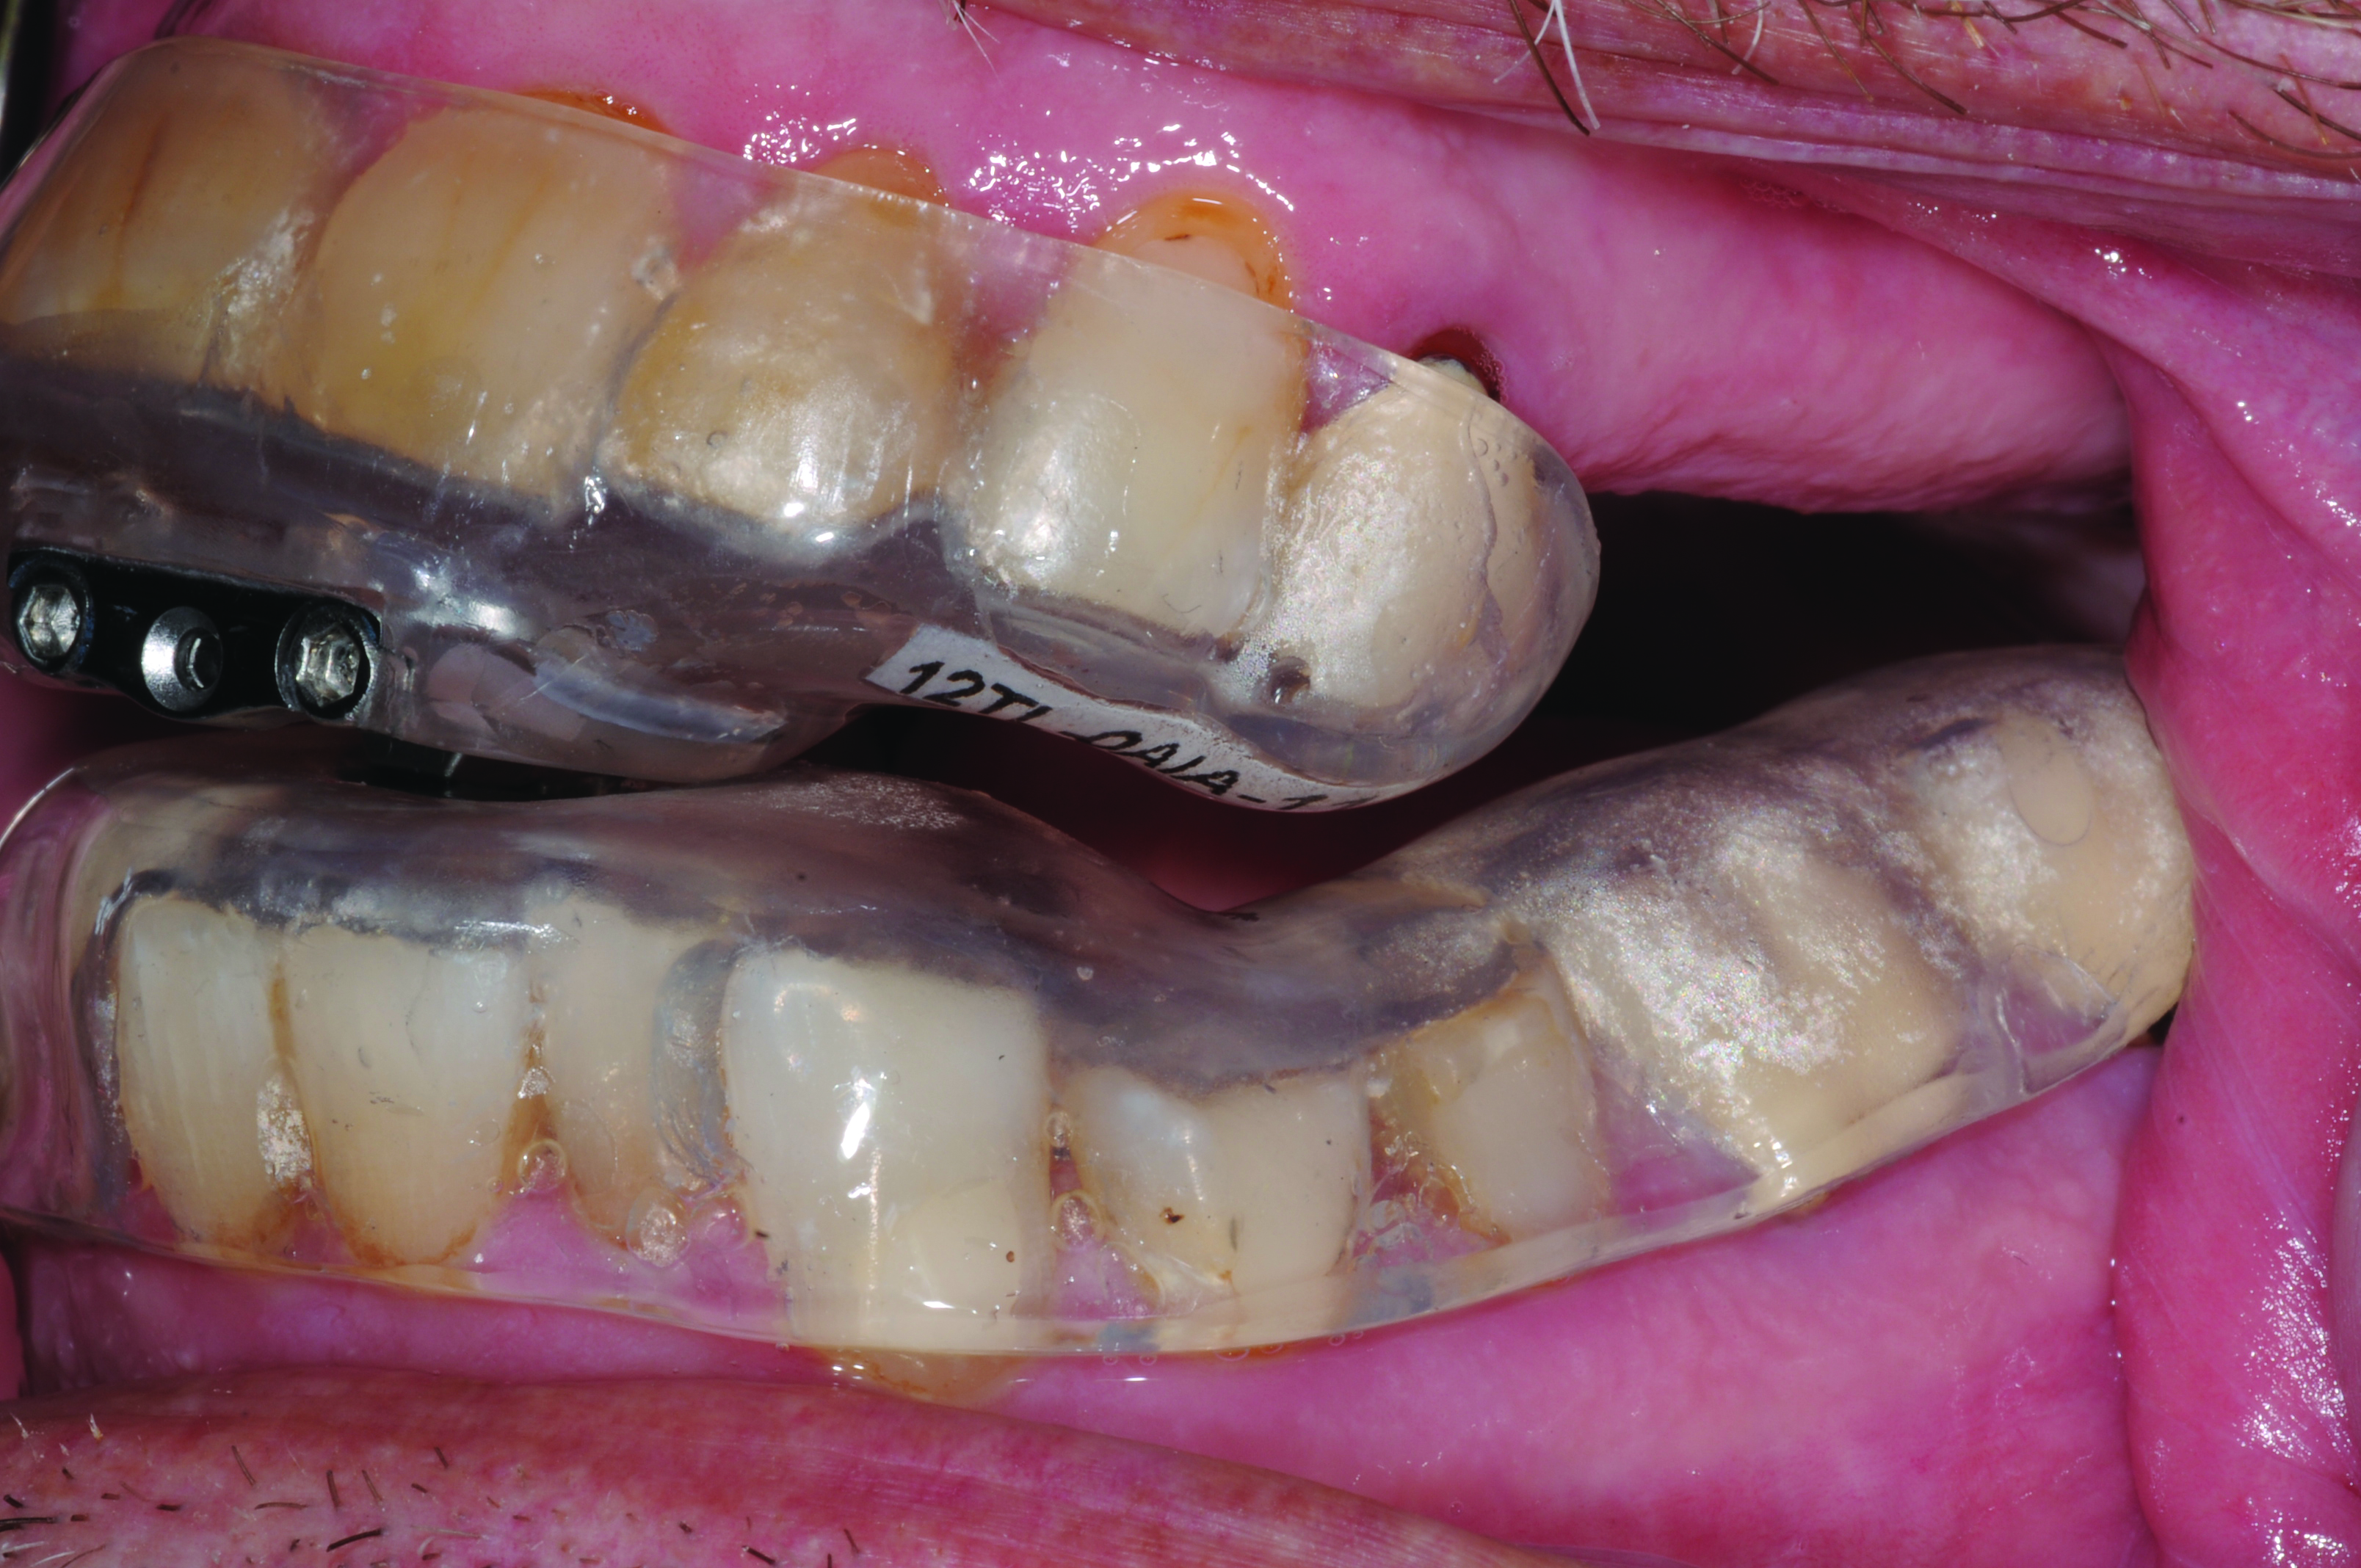

Pre-treatment Calibration

Fig 12. Casts positioned in titration trays (MATRx: http://zephyrsleep.com/) prior to fabrication of a MAD. The position of the lower tray with respect to the upper, was systematically advanced during a sleep study until sleep respiration improved a targeted amount. The calibrated titration trays are used in the same manner as a construction bite (Figure 13) in the fabrication of a MAD.

Fig 12. Casts positioned in titration trays (MATRx, zephyrsleep.com) prior to fabrication of a MAD. The position of the lower tray with respect to the upper was systematically advanced during a sleep study until sleep respiration improved a targeted amount. The calibrated titration trays are used in the same manner as a construction bite in the fabrication of a MAD (image courtesy of Doug Phillips, DDS, Asheville, North Carolina).